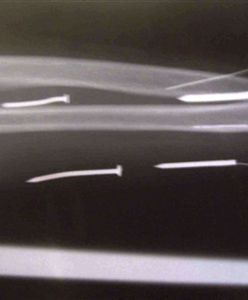

Szef ukarał pracownicę - wbił jej 24 gwoździe w ciało

Z 24 gwoździami wbitymi w ciało wróciła z Arabii Saudyjskiej mieszkanka Sri Lanki. Kobietę okaleczył jej pracodawca - informuje agencja AFP.